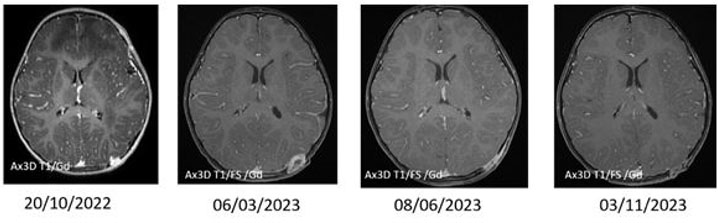

A previously healthy 2-year-old male presented with pneumonia. His workup revealed a bump on the left side of his head. He had no associated constitutional symptoms such as weight loss, fever, headaches, or seizures. He underwent imaging, including head and chest computed tomography (CT) and head magnetic resonance imaging (MRI). The latter revealed multiple ring-enhancing intra-axial lesions involving the gray-white matter junction of the bilateral frontal, left-sided parietal, left-sided occipital, and left-sided temporal lobes surrounded by significant vasogenic edema. The foci showed blooming artifact in the susceptibility weighted sequence (SWI) (Figure 1). The calvarium parietal bone showed the presence of multiple lytic intradiploic lesions associated with a soft tissue component (Figure 2). The skeletal survey did not reveal any lytic lesions. Abdominal ultrasound displayed an enlarged liver without focal lesions and no lymphadenopathy. The clinical considerations included inflammatory lesions, such as tuberculosis and fungal infection, and less likely multiple metastases. The patient is doing clinically well during follow-ups, and the MRI demonstrated improvements in intracranial lesions with no new parenchymal findings (Figure 1).

Figure 1: Intra-axial lesions with follow up AX SWI, AX 3DT1/Gd, and AX FLAIR are provided for the initial presentation and axial non-enhanced CT axial shows hyperdense foci in the bifrontal and left temporal lobes surrounded by hypodensity consistent with surrounding vasogenic edema. Follow-up after 5 months and 11 months shows interval resolution of edema on FLAIR sequence, interval decrease in the size, and enhancement of the lesions in the post-Gd sequences, and they are not visualized in the last follow-up; however, there is no change in the corresponding blooming artifact in the SWI sequence at initial presentation until last follow-up.

Figure 3: Calvaria lesions follow-up: Initial presentation with multiple calvaria lesions. The provided MRI sequence is 3D/T1/Gd, showing multiple heterogeneously enhancing lesions scattered, one of which is seen in the left posterior parietal bone. It showed interval increase in size in the follow-up performed after five months on 06/03/2023 which was later resected.